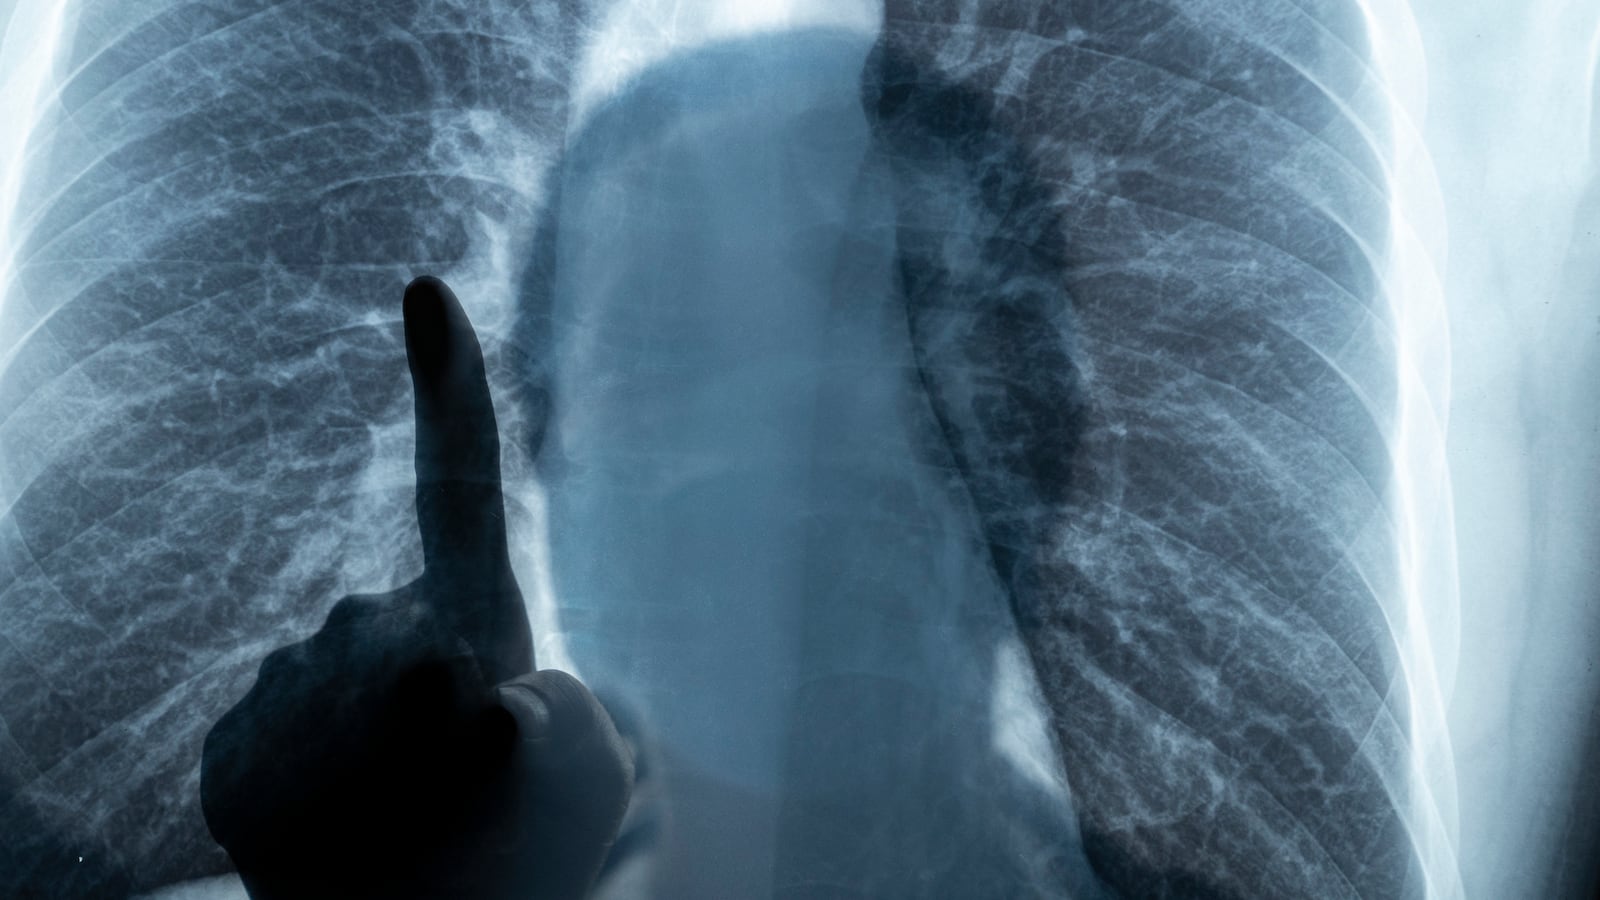

To do that, they created a deep learning model trained to view X-rays, CT scans, and mammograms from patients who self-reported their race as Asian, Black, or white. While the images contained no mentions of patient race, the team discovered that the model was able to correctly identify race with roughly 90 percent accuracy—a feat that’s virtually impossible for a human doctor to perform when looking at the same images.

There’s also the fact that a model like this can be incredibly harmful if rolled out at scale to hospitals and other practices. The medical industry continues to grapple with an incredibly grim history of medical racism and resulting malpractice. This has irrevocably shaped the way communities of color interact with (or don’t interact with) the healthcare system. If an AI were to be introduced that can somehow detect a person’s race based off of a simple X-ray, this could further deteriorate that already strained relationship.